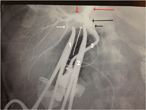

Conservative management of a traumatic common iliac venous pseudoaneurysm: a case report

Walker Lyons and others

Journal of Surgical Case Reports, Volume 2017, Issue 5, May 2017, rjx085, https://doi.org/10.1093/jscr/rjx085